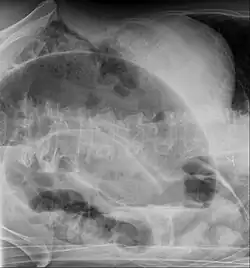

CT scan of a small bowel volvulus. It shows two juxtaposed segments of narrowing, which is the spot of mesentery rotation. The other signs indicate strangulation. -